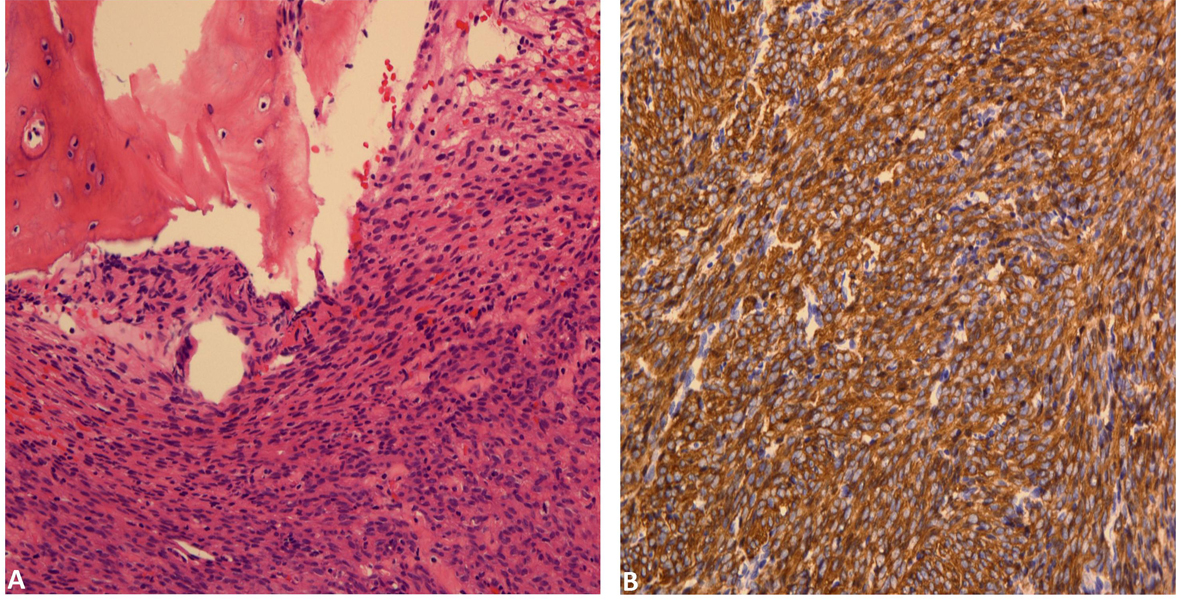

Final pathologic analysis revealed a cellular spindle cell proliferation forming fascicles with mild nuclear atypia and rare mitoses. Tumor cells invades into marrow spaces with associated bony destruction, although apparent tumor necrosis is not seen (Fig. 3A). Immunohistochemical studies showed tumor cells to be diffusely and strongly positive for smooth muscle actin (Fig. 3B), desmin and caldesmon. In addition, the morphologic features of the tumor are similar to those of the patient’s prior uterine leiomyosarcoma. Therefore, a diagnosis of metastatic uterine leiomyosarcoma involving spine is rendered.

![]() Click for large image | Figure 3. (A) Bone involved by cellular spindle cell proliferation forming fascicles with mild nuclear atypia and rare mitoses. (B). Tumor cells are diffusely positive for smooth muscle actin. |